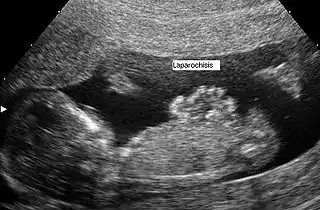

Gastrosquisis

Gastrosquisis es un tipo de defecto de nacimiento en la pared abdominal, en el cual los intestinos salen de una pequeña apertura por los lados del ombligo,[1] hay que aclarar que este orificio puede ser grande o pequeño y pueden salir otros órganos como el hígado o el estómago casi siempre a la derecha del cordón umbilical. El defecto originalmente es producido por una involución defectuosa del mesenquima embrionario en su unión con el tallo corporal, lo que resulta en una displasia de la pared abdominal. Frecuentemente puede diagnosticarse con ultrasonografía o con pruebas de líquido amniótico.

Durante la cuarta semana de desarrollo, los pliegues laterales del cuerpo se mueven hacia el centro y se fusionan en la línea media para formar la pared abdominal anterior. La fusión incompleta resulta en un defecto que permite que las vísceras abdominales protruyan a través de la pared abdominal. Los intestinos típicamente se hernian a través de los músculos rectos abdominales, es un defecto que casi siempre está a la derecha del cordón umbilical.